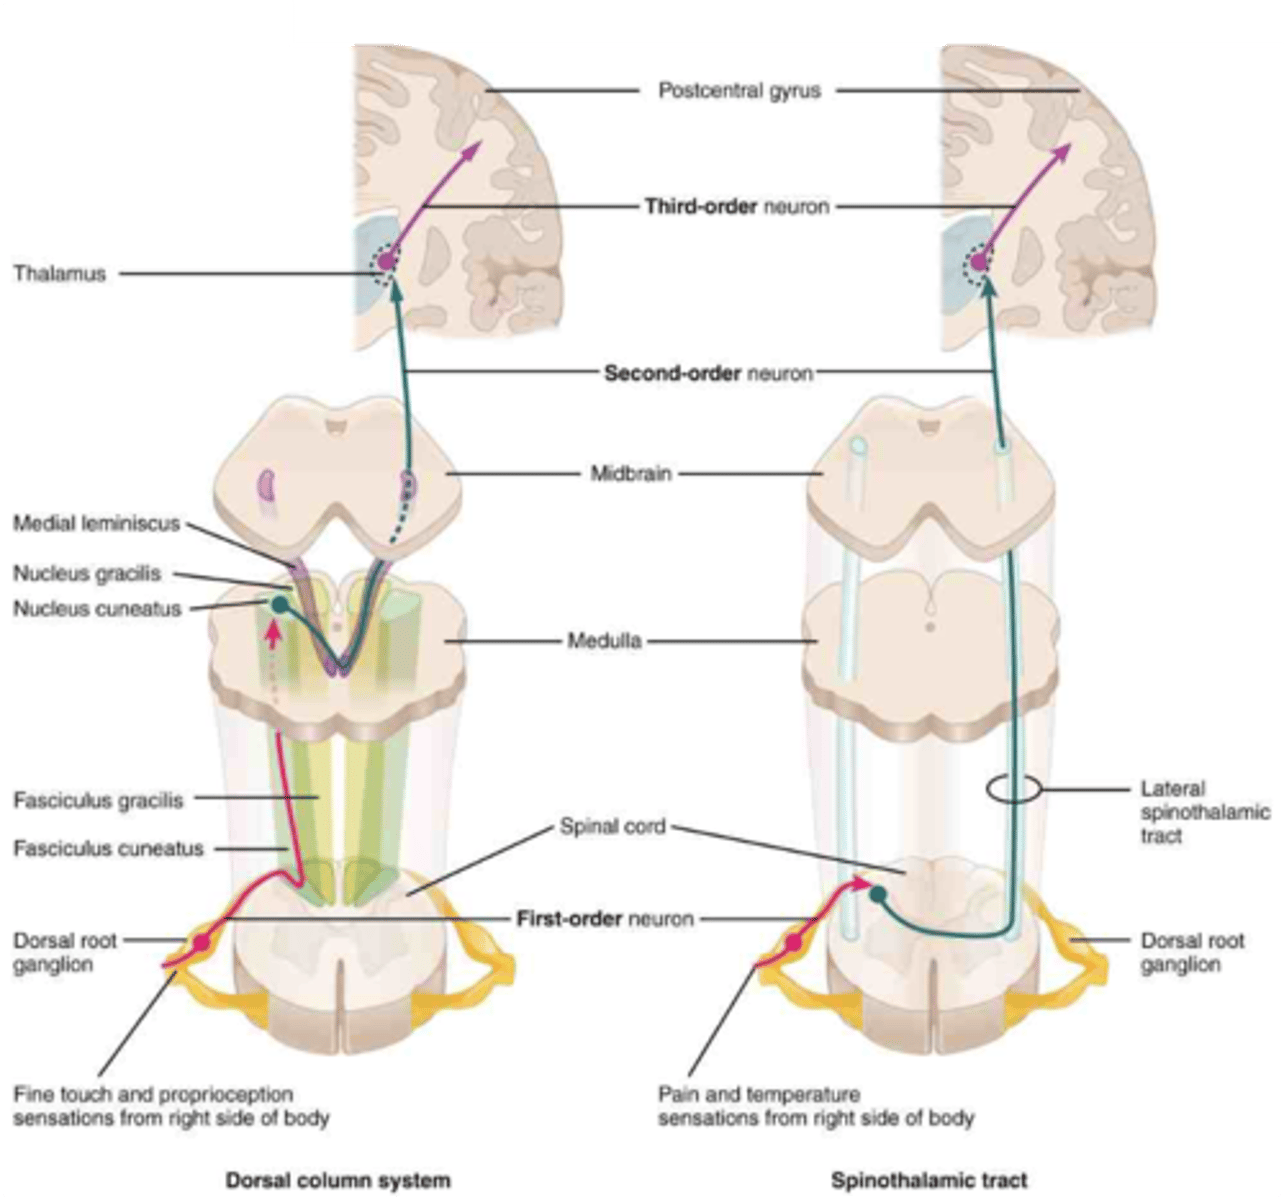

match the definition to word: lemniscus, peduncle, fasciculus

smaller bundle of axons within the CNS, often a subdivision of a larger tract

ribbon-like bundle of sensory axons, typically found in the brainstem

large stalk-like bundle of axons that connects major regions of the brain, often containing multiple tracts of mixed function

fasciculus

lemniscus

peduncle

what term refers to a cross in the midline?

what term refers to staying on the same side?

what term refers to being on the opposite side?

decussate —> midline

ipsilateral —> same side

contralateral —> opposite side